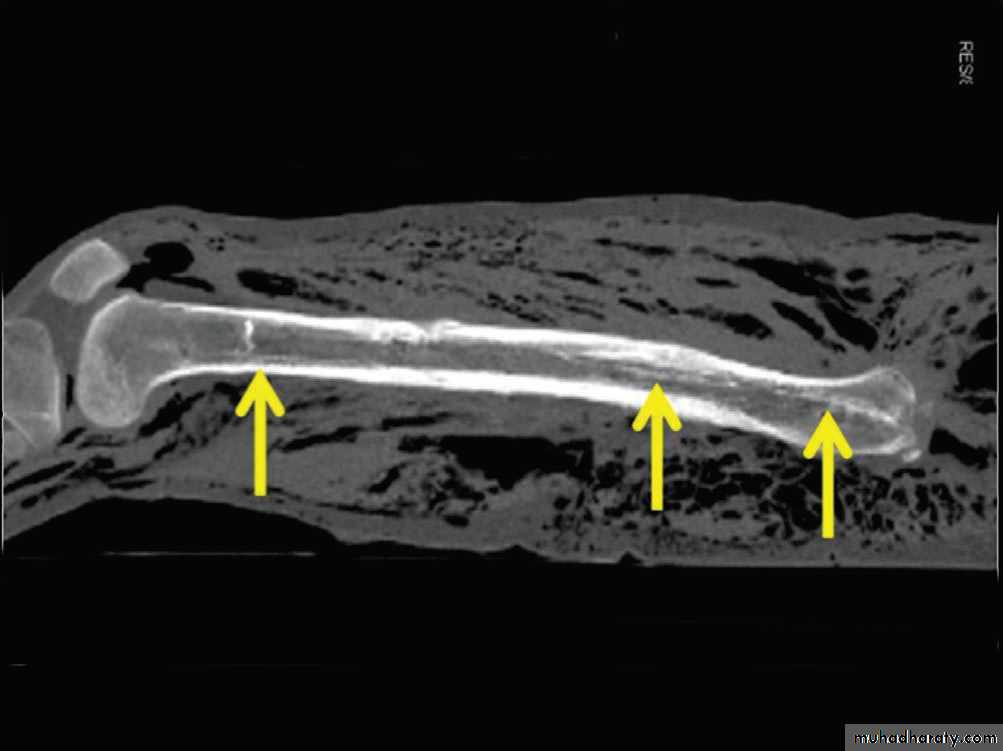

60تعيين سبب الموت من العظام: يمكن معرفة سبب الوفاة من خلال فحص العظام اذا كان السبب المؤدي للوفاة قد اصاب العظام وترك اثاره عليها كما هو الحال في اصابات الطلق الناري التي تصيب الراس وتترك اثرها في عظام الجمجمة. الا انه ليس من الضروري وجود اصابات عظمية مترافقه مع الضرر الكلمي , اذ قد تكون الاصابة الكلمية قد تناولت الانسجة الرخوة كما هو الحال في الاصابات النحرية والاصابات الطعنية في الصدر. و الاصابات المارة من بين الاضلاع لتصيب القلب او الرئتين وتؤدي الى تمزقهما.

63• تقدير الزمن المنقضي على الوفاة من خلال فحص العظام: تقاوم العظام التفسخ فترة طويلة, فتبقى متصلة مع بعضها على شكل هيكل عظمي بواسطة الاربطة. تمتد هذه الحالة من بضعة اسابيع حتى ثلاثة اشهر. خلال ثلاثة شهور اخرى تزول الاربطة و تنفصل العظام عن بعضها. في هذة المرحلة تكون العظام شحمية الملمس وذات رائحة زنخة. تزول الرائحة الزنخة تدريجيا في وقت اقصاه منتصف السنة الثانية بعد الوفاة. بعدها يجف العظم ويتحول ملمسه الى ملمس الجبس.